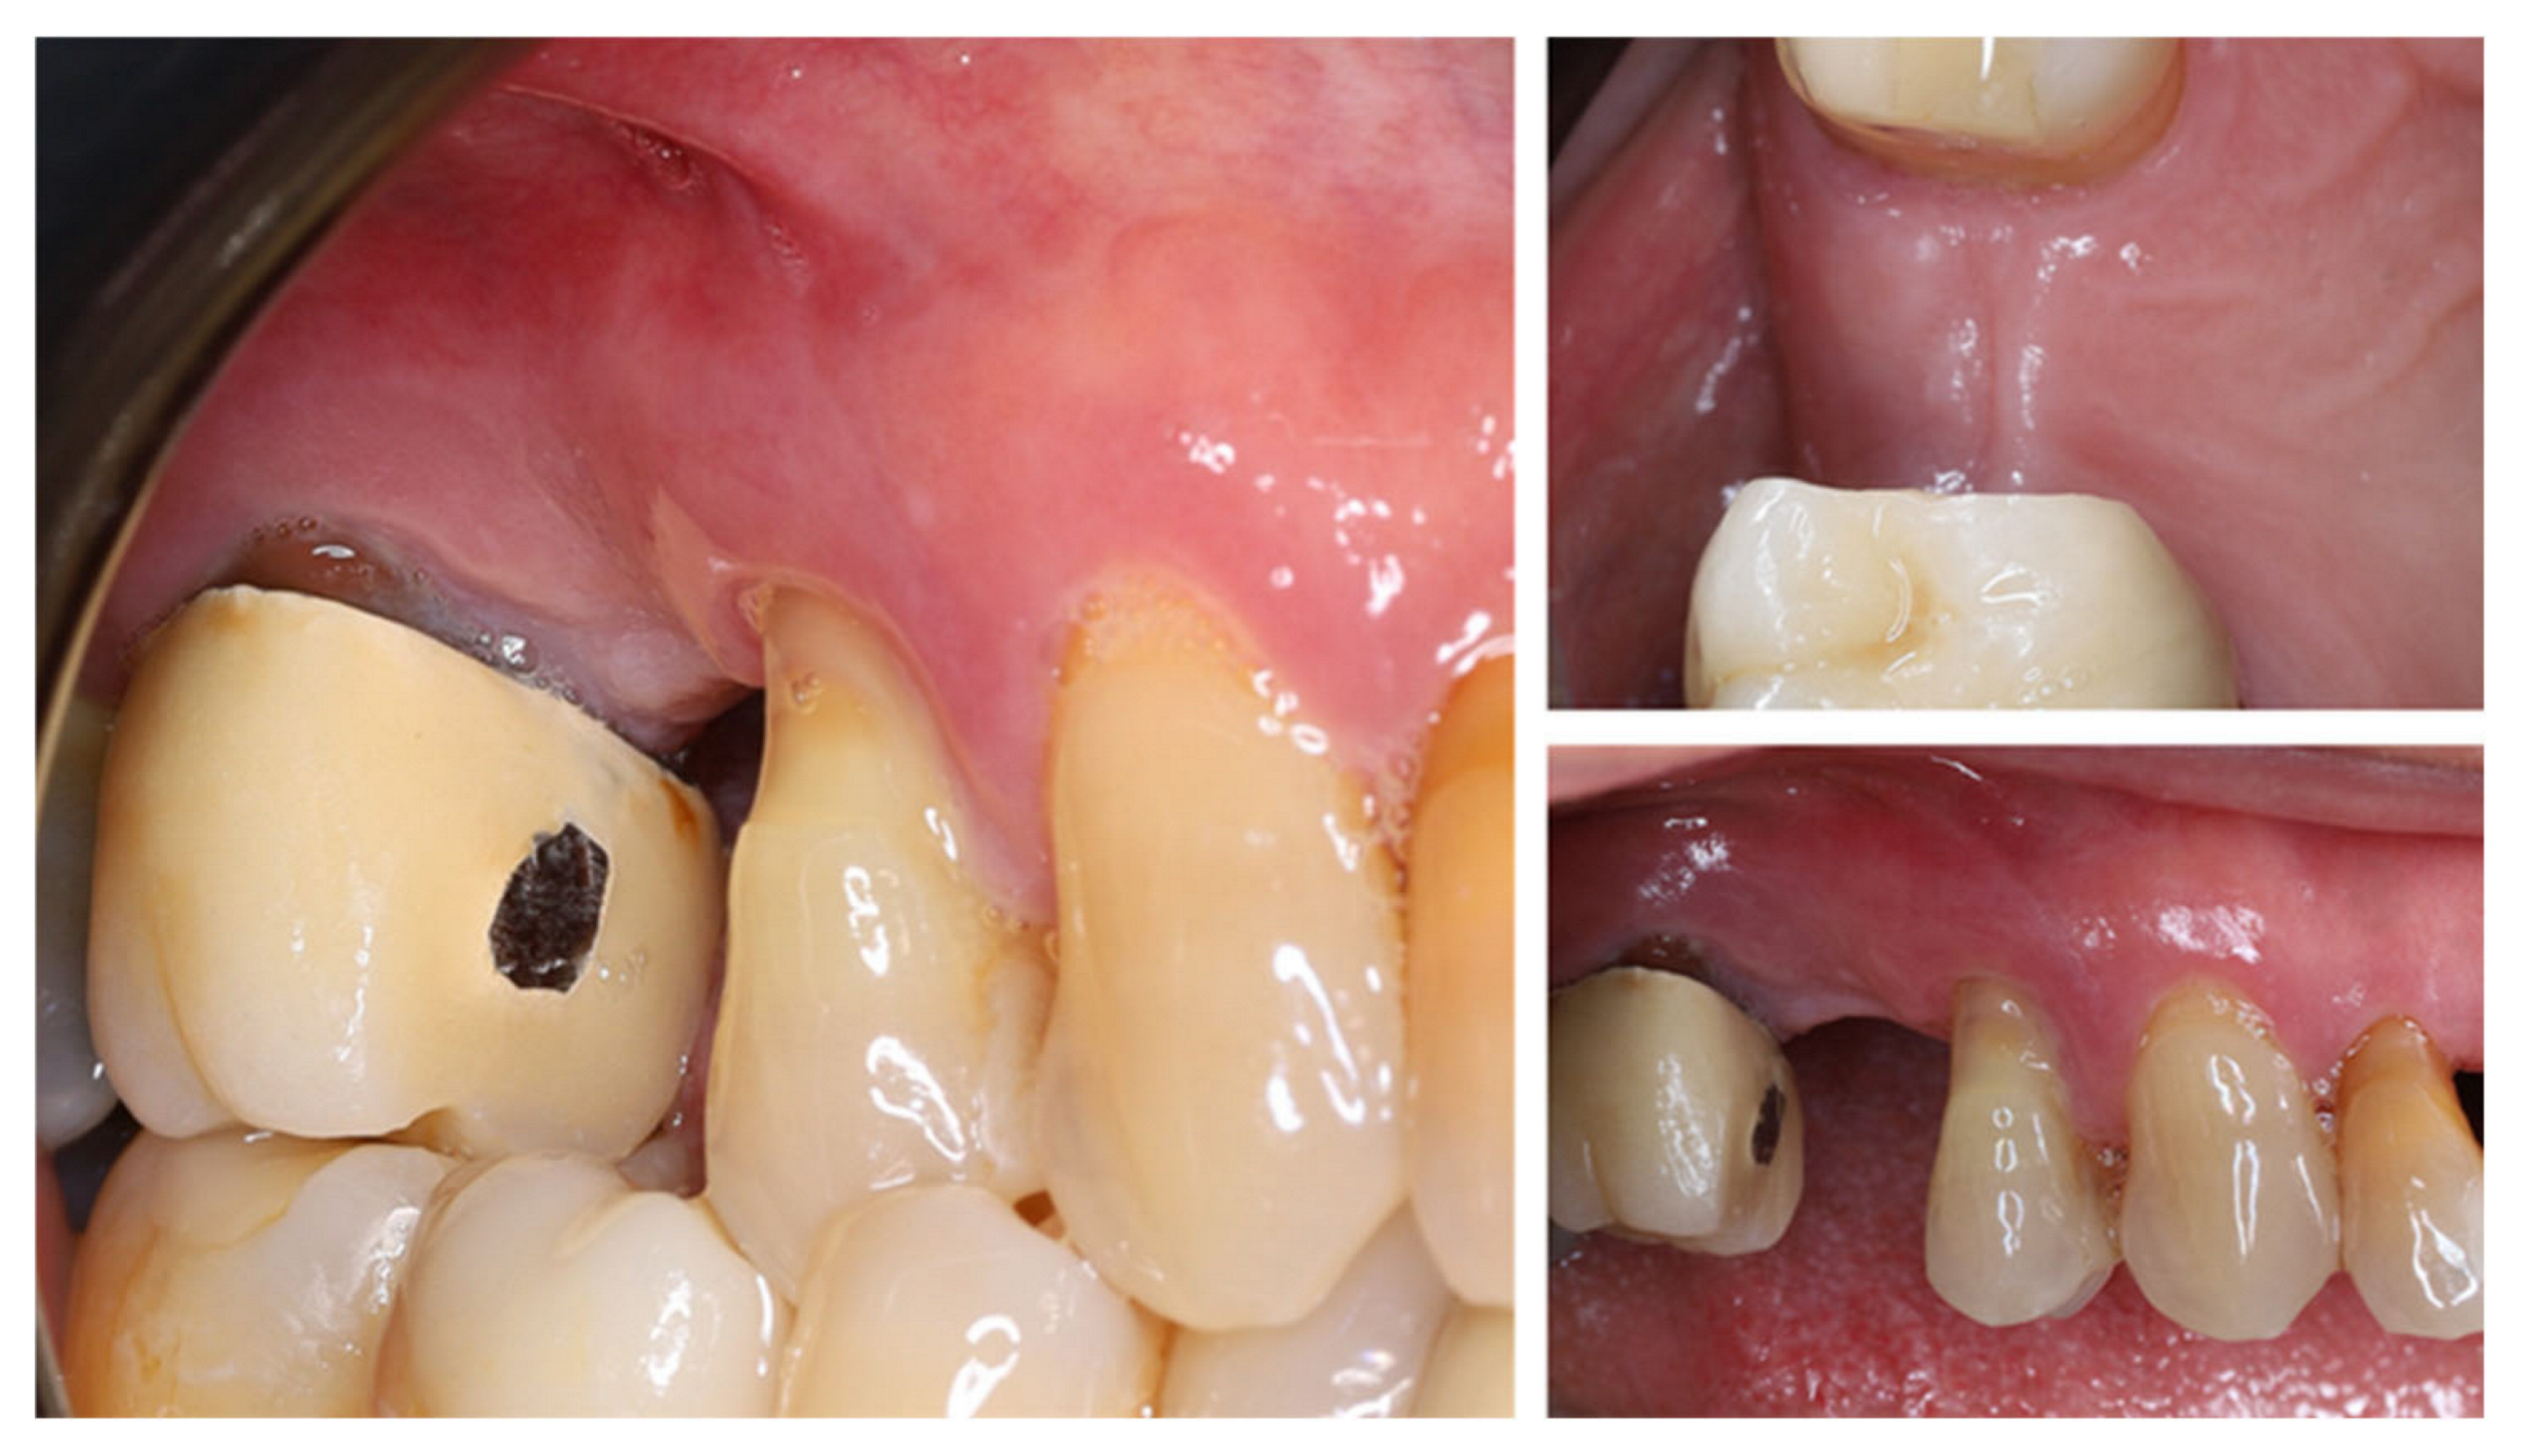

| Timepoint | Horizontal Thickness (mm) | Vertical Thickness (mm) | Clinical/Radiographic Findings | |

|---|---|---|---|---|

| 1 | Baseline (Day 0) | 2.3 | 2.4 | Initial thin buccal tissue |

| 2 | 2 weeks post-op | Uneventful healing, stable mucosal margin | ||

| 3 | 3 months post-op (with provisional) | 3.4 | 3.4 | Increased thickness, stable bone and mucosa |

| 4 | 4 months post-provisional | 3.5 | 3.6 | Stable peri-implant mucosa around provisional crown |

| 5 | 8 months post-op (final crown) | 3.5 | 4.1 | Final crown placed, harmonious soft tissue contours, and stable crestal bone |

| 6 | 14 months post-definitive | Long-term stability of soft tissue and crestal bone confirmed |